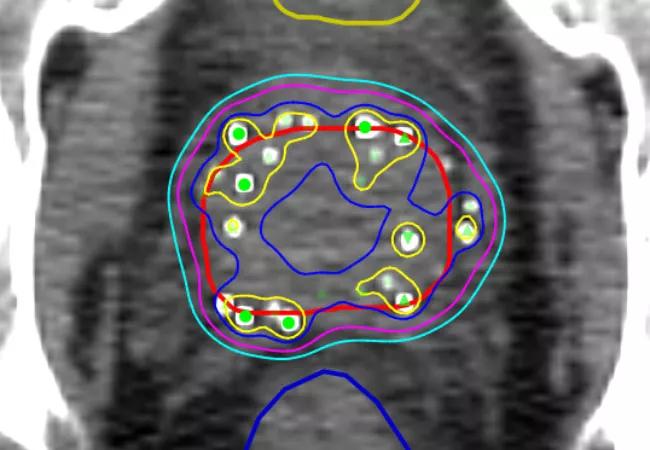

Localized treatment — adding brachytherapy to external beam radiotherapy — appears to improve survival outcomes for men with high-risk prostate cancer, according to a large retrospective study by Cleveland Clinic researchers published in JAMA.

In the study, a retrospective review of 1,809 patient records from the Cleveland Clinic and 11 other tertiary care centers around the country plus Norway, researchers compared the clinical outcomes of men with Gleason score 9-10 prostate cancer who had received one of three treatment modalities:

• Radical prostatectomy (RP) (n = 639); median age 61 years.

• External beam radiotherapy plus androgen deprivation therapy (EBRT) (n = 734); median age 67.7 years.

• EBRT plus brachytherapy boost (EBRT+BT) (n = 436); median age 67.5 years.

Contrasting this shift toward surgery, however, the analyses found that the EBRT+BT group fared better across all three outcomes, with a significantly lower adjusted five-year prostate cancer-specific mortality rate at 3 percent, compared to 12 percent for RP and 13 percent for EBRT. For distant metastasis, adjusted five-year rates were 8 percent for EBRT-BT, compared with 24 percent for both RP and EBRT. As for adjusted 7.5-year all-cause mortality, the rates were 10 percent for EBRT-BT, compared with 17 percent for RP and 18 percent for EBRT.